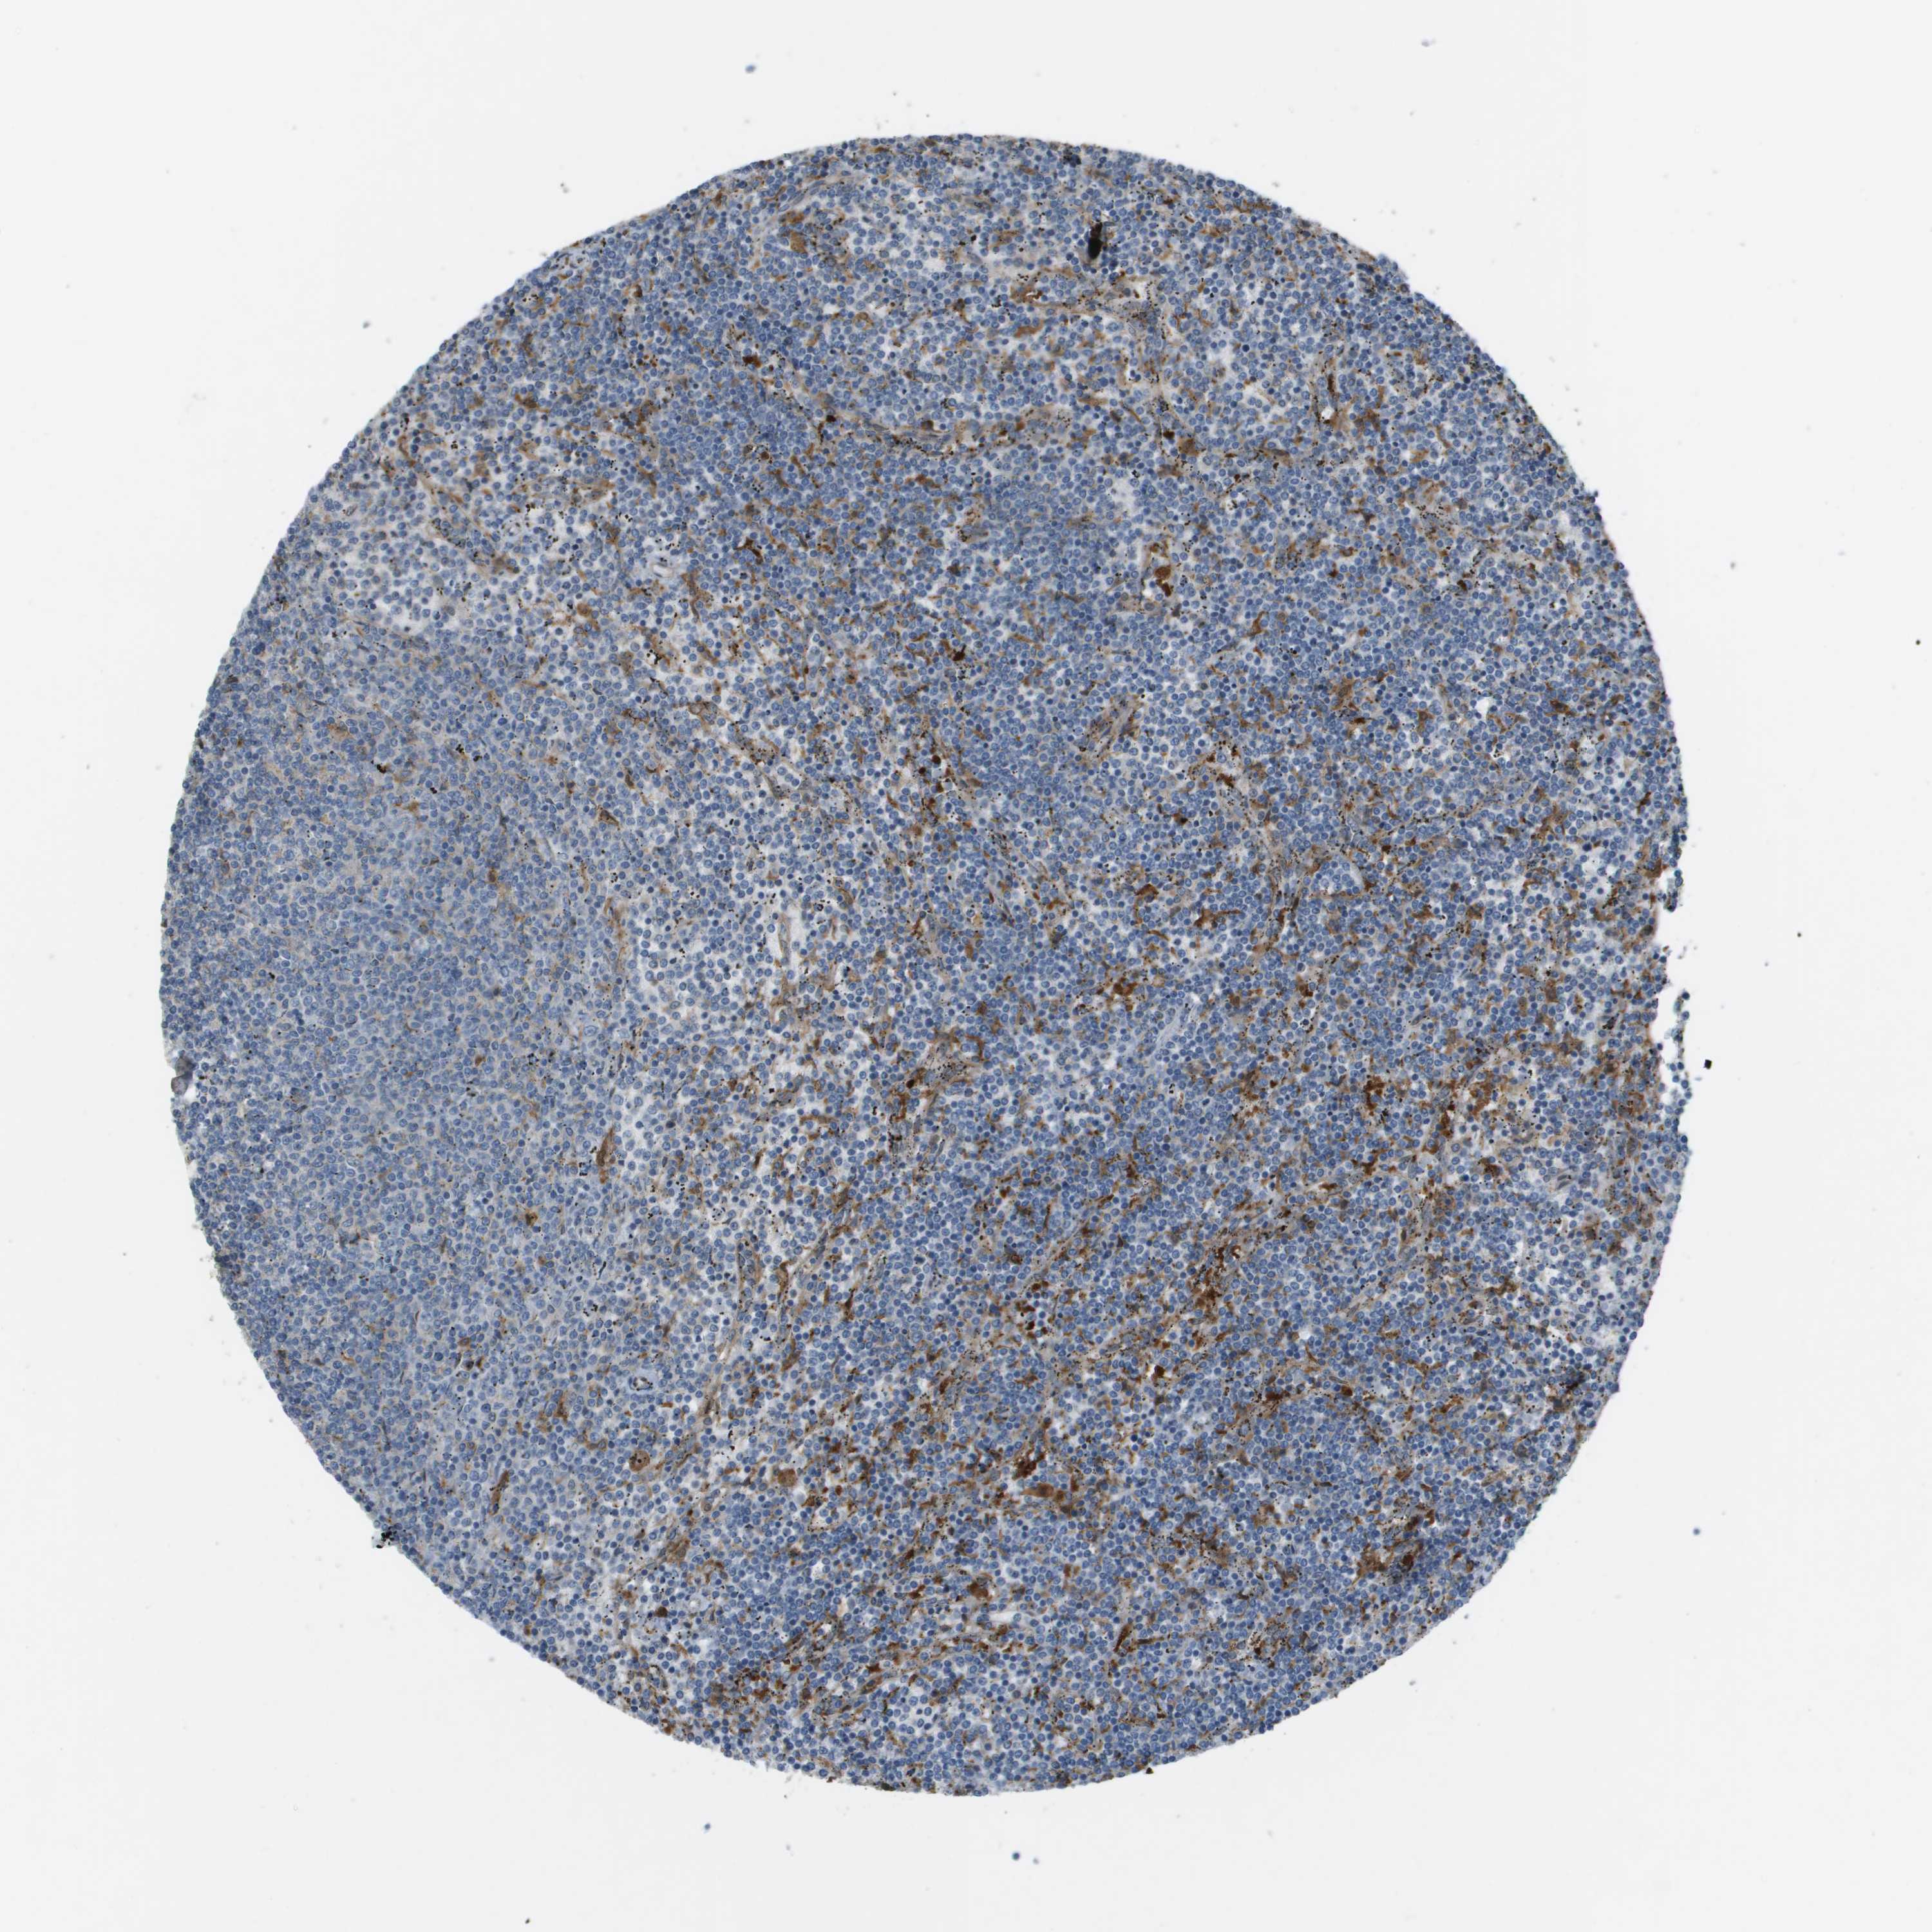

CANCER LYMPHOMA Show tissue menu

LYMPHOMA - Protein expressioni

A mouse-over function shows sample information and annotation data. Click on an image to view it in a full screen mode. Samples can be filtered based on level of antibody staining by selecting one or several of the following categories: high, medium, low and not detected. The assay and annotation is described here.

Antibody stainingi

Antibody staining in the annotated cell types in the current human tissue is reported as not detected, low, medium, or high, based on conventional immunohistochemistry profiling in selected tissues. This score is based on the combination of the staining intensity and fraction of stained cells.

Each image is clickable and will lead to virtual microscopy that enables deeper exploration of all samples and also displays staining intensity scores, fraction scores and subcellular localization as well as patient and tissue information for each sample.

Antibody HPA070456

Antibody CAB017616

Staining

High

Medium

Low

Not detected

Intensity

Strong

Moderate

Weak

Negative

Quantity

>75%

75%-25%

<25%

None

Location

Nuclear

Cytoplasmic/membranous

Cytoplasmic/membranous,nuclear

Malignant lymphoma, non-Hodgkin's type, Low grade

Malignant lymphoma, non-Hodgkin's type, High grade

Hodgkin's disease, NOS